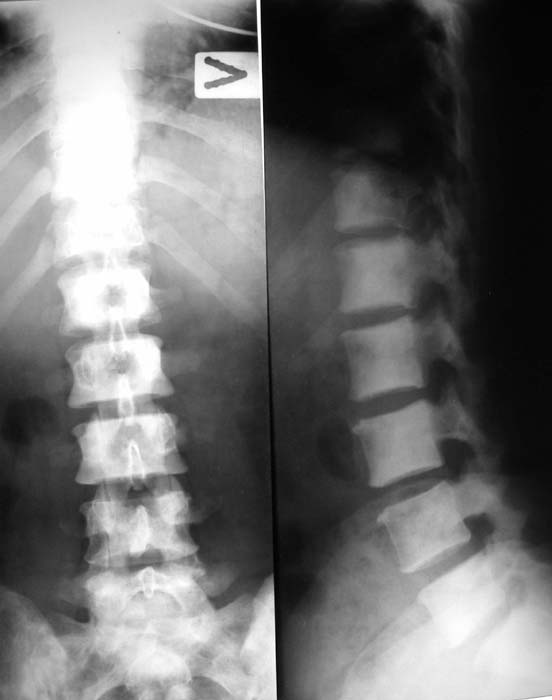

Женщина, 46 лет.

В течение четырех месяцев жалобы на боли в спине.

При МРТ (29.10.06) обнаружены диффузно-очаговые изменения в пояснично-крестцовом отделе позвоночника предположительно вторичного характера.

Остеосцинтиграфия 4.12.06. - активный остеобластический процесс в поясничном, нижнегрудном отделах позвоночника, костях таза. Местными онкологами онко-процесс исключен. Фтизиатрический и онкогематологический диагнозы исключены.